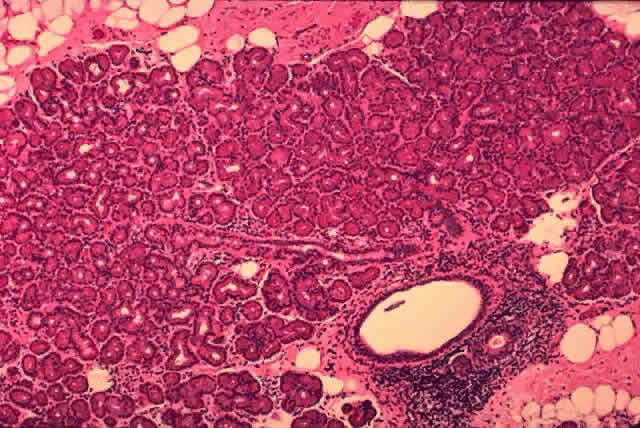

Each lobule consists of a complicated grape-like (Fig. 14) arrangement of acini. Each acinar unit (Fig. 15) consists of a central lumen, a continuous inner layer of columnar secretory epithelial cells, and a surrounding interrupted outer layer of irregularly shaped myoepithelial (basket) cells.9

Fig. 14. Tubuloracemose architecture of the lacrimal gland. Interlobular fibrovascular connective tissue (large arrow) separates the lobules of acinar tissue (small arrow). (H & E, original magnification × 5; Courtesy of Ralph Eagle, MD, Philadelphia, PA)

The acinar secretory cell typically has a basally located nucleus with one or two nucleoli, as seen with electron microscopy. The predominant structures in its cytoplasm are the numerous zymogenic secretory granules located mainly in the apical or midportions of the cell9 (see Fig. 15).

The secretory granules vary in shape from round to oval and have a surrounding membrane. The secretory granules vary in electron density from homogeneous (electron-dense) to finely granular (less electron-dense).10 The number of granules in the cytoplasm varies from cell to cell. The size of the secretory granules also varies, the larger ones being located in the more peripheral portion of the lobule. Although chemical studies show that the secretory granules of the lacrimal gland contain both serous proteins and mucous polysaccharides, the predominance of dense granules containing protein suggest that the serous type of secretion is the primary function of the lacrimal glands.11